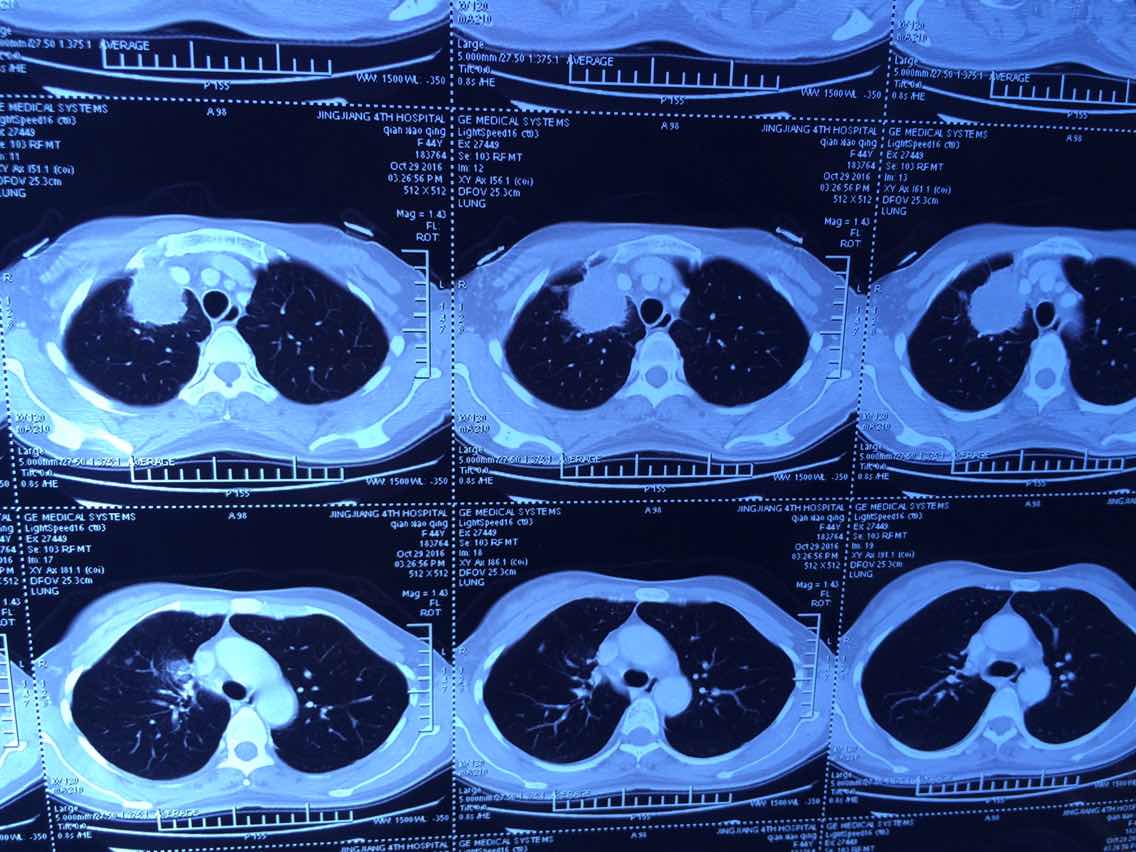

陈医生,这是2016.10.26的ct看看拍的对不

2

举报

2017-10-31 10:10:42 有用(0)

回复(0)

3

2017-10-31 10:11:05 有用(0)